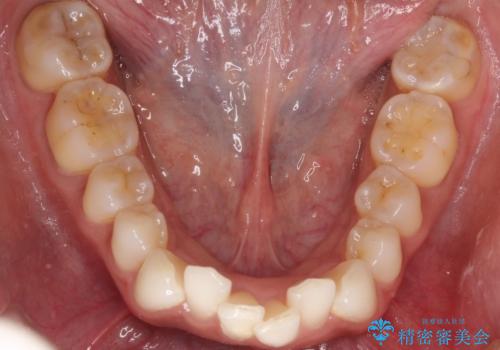

精密検査の結果、歯を並べるためのスペースが不足していましたが、抜歯をせずに改善したいというご希望があったため、IPR(歯の側面をわずかに削る処置)と、奥歯を後ろに動かす「遠心移動」を組み合わせる計画を立案。透明なマウスピース装置であるインビザラインを使用し、無理のない範囲でスペースを確保しながら歯列を整えることとしました。

治療では、マウスピースの設計に基づき、奥歯から順に後ろへ移動させる遠心移動を行い、前歯のためのスペースを作りました。同時に、数箇所の歯の間にIPRを施すことで、歯の健康に影響のない範囲で精密に隙間を確保しました。

1年半の治療期間を経て、重なり合っていた前歯はスムーズに整列し、理想的なアーチ状の歯並びへと改善されました。抜歯を行わずに治療を完了したことで、噛み合わせのバランスを維持しながら、審美性を大きく向上させることができました。現在は保定期間に入り、美しい状態を維持されています。